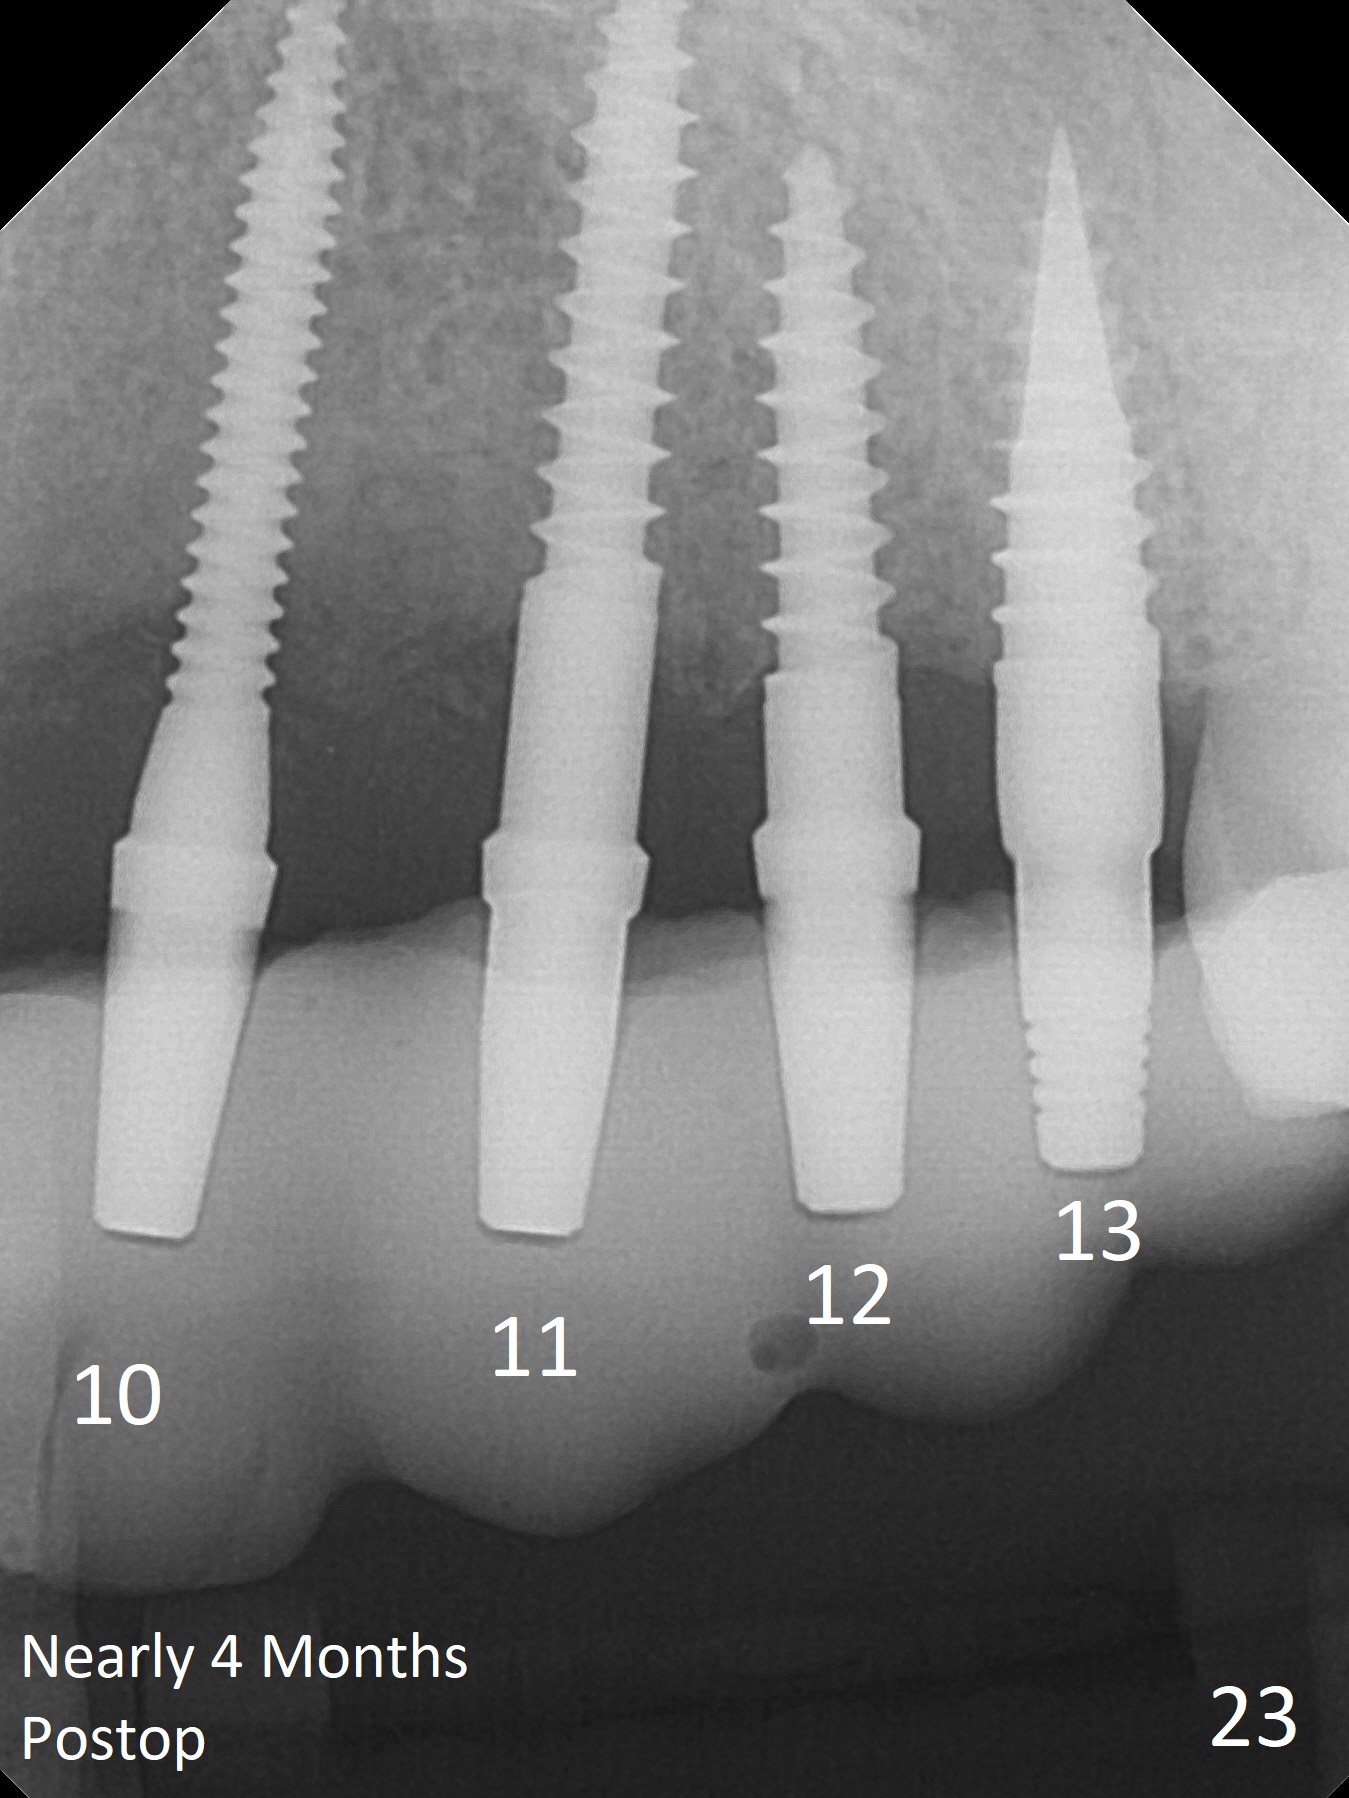

Fig.16: 2x14(2), 2.5x14(4), 2.5x12(2) and 3x10(2) mm implants are placed at #11-13. With relatively correct position of each implant, it would be easy to fabricate a splinted 6-unit provisional (Fig.23, nearly 4 months postop).